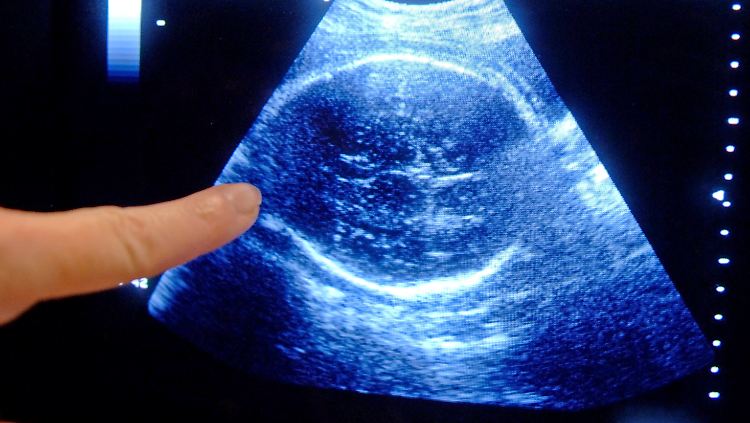

Drei Ultraschall-Untersuchungen gehören zum Standard - eines pro Trimester. Viele Frauen lassen aber fünf und mehr vornehmen.

(Foto: picture alliance / dpa)

Zu viel Ultraschall, zu viele Untersuchungen: Fast alle Schwangeren nehmen Vorsorgemaßnahmen in Anspruch, die in den Richtlinien gar nicht vorgesehen sind. Hierzu zählen etwa mehr als drei Ultraschalluntersuchungen und spezielle Blut- oder Herztonmessungen. Dies zeigt eine aktuelle Studie der Bertelsmann-Stiftung, für die knapp 1300 Mütter kurz nach der Geburt befragt wurden.

Bei der Befragung gab fast die Hälfte der Frauen mit normaler Schwangerschaft an, mehr als fünf Ultraschalluntersuchungen gemacht zu haben. Die Mutterschaftsrichtlinien sehen aber nur drei vor. Auch scheint eine spezielle Herzton- und Wehenmessung (CTG/Kardiotokographie) längst zur Routine zu gehören. Obwohl diese Untersuchungsmethode nur bei drohenden Frühgeburten und anderen Auffälligkeiten vorgesehen ist, ließen 98 Prozent die Untersuchung durchführen - im Schnitt sogar öfter als vier Mal.